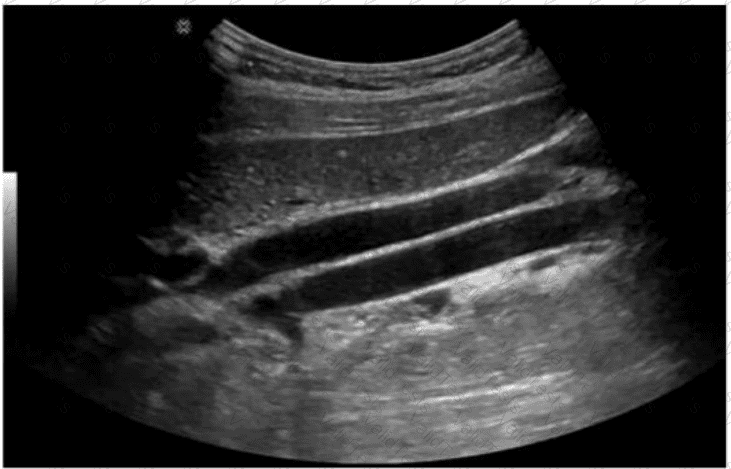

Which condition is most consistent with the sonographic appearance in this image of the abdominal wall?